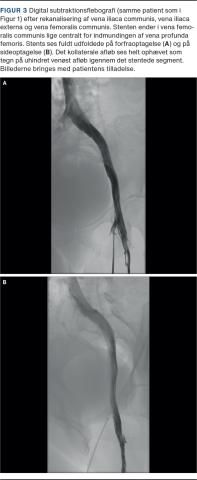

Endovaskulær behandling, dvs. ballondilatation og stentning, udføres for at genetablere det centrale venøse afløb fra ekstremiteten. Indsættelse af en stent forudgås af prædilatation af det obstruerede venesegment med højtryksballon og efterfølges af efterdilatation af selve stenten, ligeledes med højtryksballon (Figur 2 og Figur 3). Dilatationen er smertefuld, og indgrebet foretages derfor ofte i generel anæstesi.

Billede